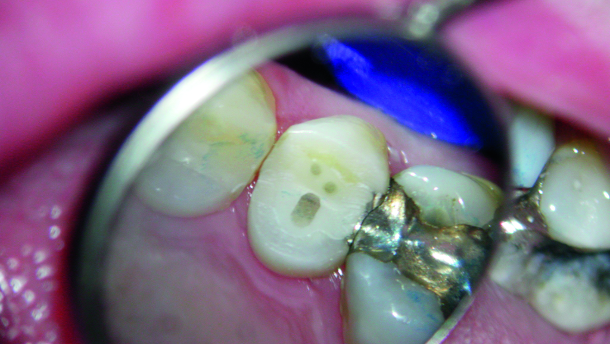

Post preparation of the root canal space must not remove additional dentine, as this contributes to a reduced fracture toughness (Fig. 1). Ree et al. state that ‘no additional dentin should be removed beyond what is necessary to complete the endodontic treatment’.[11] If this concept is to be adhered to clinically, then of course the use of parallel sided posts must be eliminated from our clinical protocol, as these posts usually require removal of sound apical radicular dentine, creating sharper internal line angles, resulting in a weakened root and a higher root fracture risk (Fig. 2).[12] Moreover, the parallel post does not complement the tapered shape of the prepared canal, resulting in excess luting composite in the coronal aspect of the canal, which can decrease bonding efficacy and decrease dislocation resistance (Fig. 3).[13] If we adhere to the concept of minimal dentine removal in the root, and if we recognise that most root canals are ovoid in shape, then a wholly different treatment approach than what we have been taught in the past is indicated. Boksman et al. have recommended utilising a tapered master quartz fibre post (Macro-Lock Post Illusion X-RO, RTD St. Egreve, France) with additional Fibercones (RTD St. Egreve, France) placed into the irregularity (lateral spaces) of the canal (Figs. 4 & 5).[14] This technique is similar to using a master gutta-percha point with accessory gutta-percha points, which is well understood. Utilising this approach provides several clinical advantages, [15–19] including more anti-rotational resistance, decreased volume of composite or cement lateral to the post to decrease the C and S Factor constraints (volumetric shrinkage), better adhesion to the root canal walls resulting in decreased microleakage and increasing resistance to dislodgement, as well as decreased likelihood for lateral perforation. The combination of a post, or multiple posts, that transmit light efficiently, with sufficient extended light curing time/output, results in better composite polymerisation.